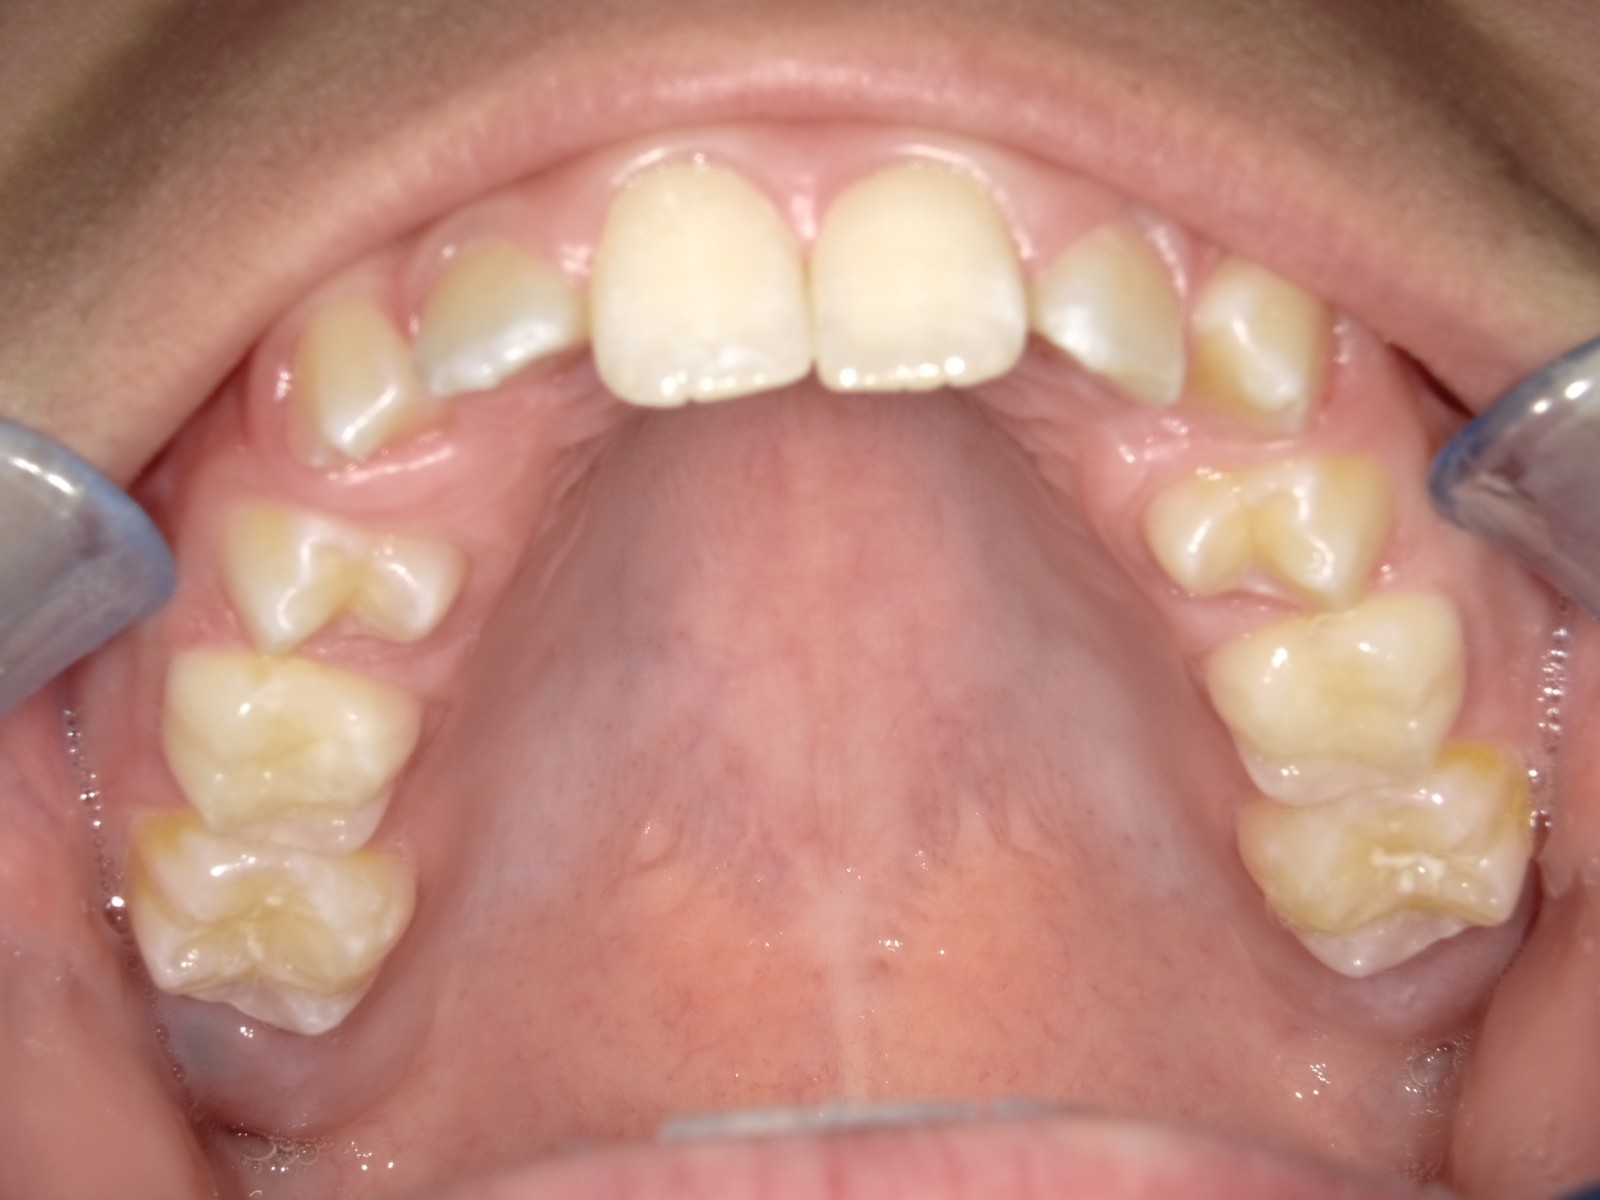

7-12 maand Distalizers